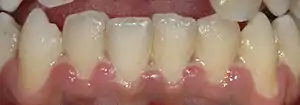

Dentin hypersensitivity is a sharp, short-lasting dental pain occurring in about 15% of the population,[16] which is triggered by cold (such as liquids or air), sweet or spicy foods, and beverages.[17] Teeth will normally have some sensation to these triggers,[18] but what separates hypersensitivity from regular tooth sensation is the intensity of the pain. Hypersensitivity is most commonly caused by a lack of insulation from the triggers in the mouth due to gingival recession (receding gums) exposing the roots of the teeth, although it can occur after scaling and root planing or dental bleaching, or as a result of erosion.[19] The pulp of the tooth remains normal and healthy in dentin hypersensitivity.[10]:510

Many topical treatments for dentin hypersensitivity are available, including desensitizing toothpastes and protective varnishes that coat the exposed dentin surface.[16] Treatment of the root cause is critical, as topical measures are typically short lasting.[10]:510 Over time, the pulp usually adapts by producing new layers of dentin inside the pulp chamber called tertiary dentin, increasing the thickness between the pulp and the exposed dentin surface and lessening the hypersensitivity.[10]:510